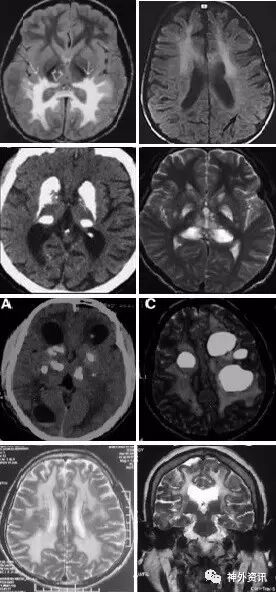

(重要申明:以下每个部分会配磁共振图片,因疾病和影像之间存在同病异象、同像异病,为避免误导,图片不标注疾病,其各自鉴赏,另其中的部分图片来源于网络,有疑问可与本人联系)

代谢性脑病的原因很多,包括氨基酸、有机酸、脂肪酸、糖等代谢异常,以及线粒体功能障碍等,导致高氨血症、低血糖、酸中毒和能量缺乏,引起脑功能障碍。我们在临床上看到的有缺血缺氧性脑病、低血糖致白质脑病、肝性脑病、肾性脑病、Wernicke脑病、线粒体脑病等。中枢神经系统受累的病灶在磁共振上可出现各种表现。

脱髓鞘,多发性硬化(MS)、视神经脊髓炎(NMO)、急性播散性脑脊髓炎(ADEM)、MOG相关性脱髓鞘病变、自身免疫性脑炎、CNS血管炎、神经系统结节病、Susac's Syndrome、Clippers’综合症、桥本氏脑病等。还有如急性、亚急性的放疗损伤等。